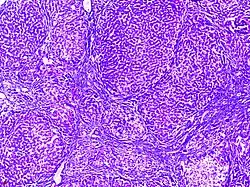

![]() |

Follicular lymphoma | Micrograph showing a small B-cell lymphoma compatible with follicular lymphoma. H&E stain. | Category: Histopathology of follicular lymphoma | Follicular lymphoma |